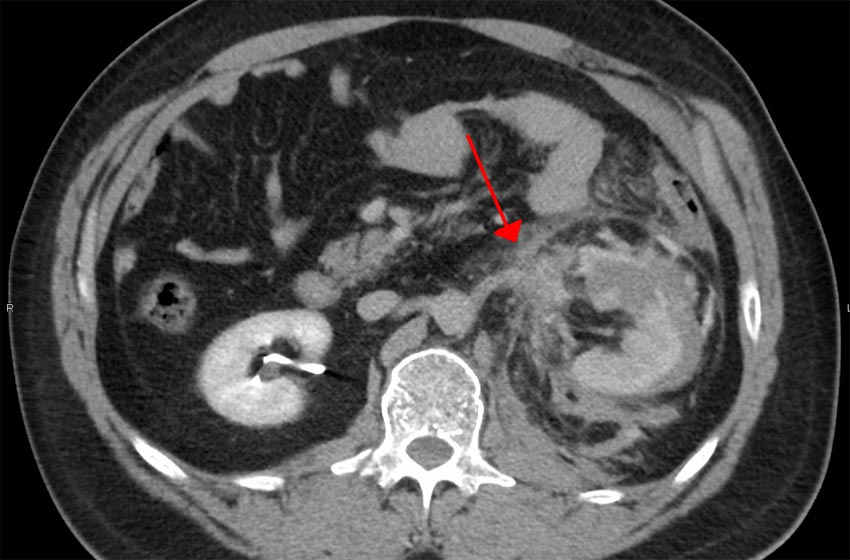

La nefrectomía radical con trombectomía tumoral de vena cava inferior (VCI) requiere una amplia planificación quirúrgica para maximizar las probabilidades de éxito.